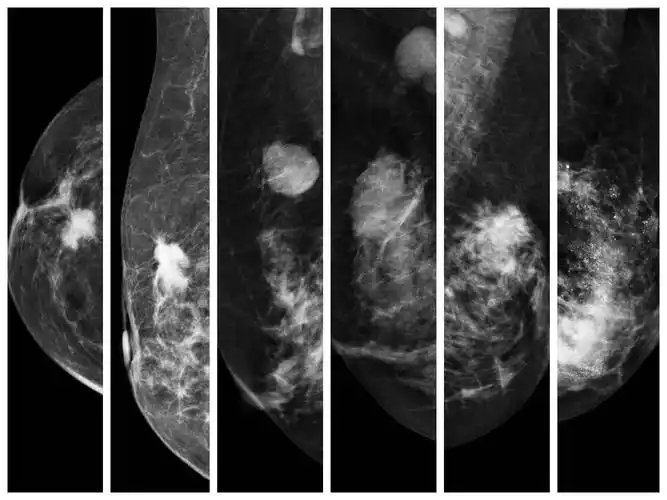

97乳腺癌临床表现:从早期—到晚期96早期可能是一个无痛性肿块,无

乳腺癌的早期症状 1,肿块或伴有疼痛 为95%乳腺癌病人的首发症状

早期乳腺癌的常见表现:无痛单个小肿块,局部隆起,酒窝征

因发现右乳肿块一月入院,术前钼靶及彩色b超均呈典型的乳腺癌表现

早期乳腺癌的症状主要包括乳房肿块,乳头溢液以及乳房皮肤病变的症状.